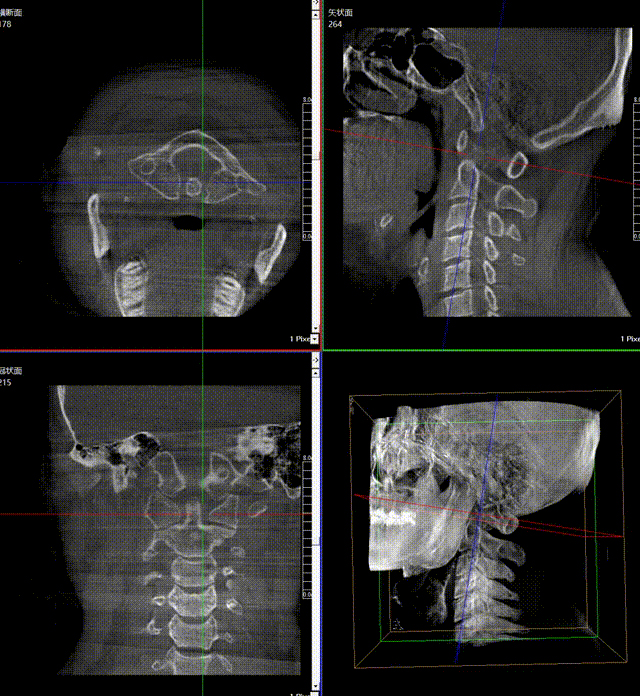

通常上頸椎的手術(shù)是非常復(fù)雜的,因?yàn)獒t(yī)生要把釘子打在上頸椎這樣一個(gè)很狹小的通道里面,周圍都是重要的神經(jīng)血管,一旦損傷到頸椎,就有可能造成病人的死亡。隨著醫(yī)學(xué)影像技術(shù)的不斷發(fā)展,在三維影像的引導(dǎo)下,整個(gè)打進(jìn)去的通路能夠完全的展現(xiàn)在我們的眼睛里,讓這種復(fù)雜的手術(shù)變得簡(jiǎn)單了,更多的醫(yī)生就可以去開展這樣的手術(shù)了,也會(huì)有越來越多的病人從中獲益。